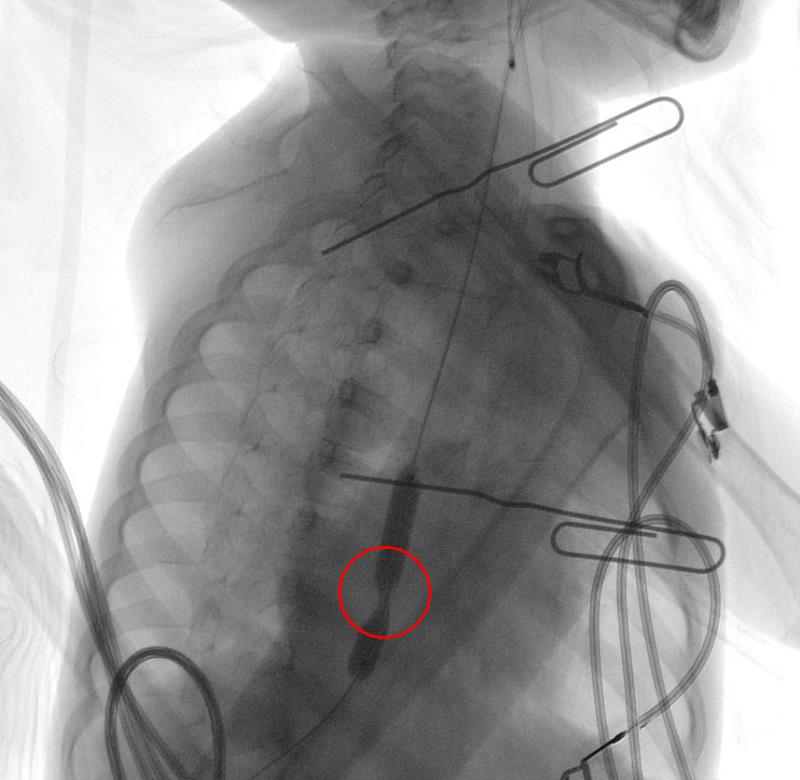

小妍自今年八月初起,逐漸只吃得下流質食物,甚至會吃不下直接吐出來,回診經上消化道攝影與胃鏡檢查,觀察到食道狹窄到最細的鼻胃管都無法通過,經胸腔到胃部的電腦斷層,發現狹窄最長達3.5公分以上,並確認嚴重狹窄區段至少有兩處。張雲傑表示,異物誤食在急診室是相當常見的情況,只是一般人嚐到味道不對或感覺到不適就會立刻停止,而像小妍一次吞入40~50c.c.的高腐蝕性液體,是他十年來在臨床看到誤食最大量的案例;由於強鹼接觸黏膜時帶來的灼熱感,相比起強酸較不強烈,加上小妍在喝下前的心態是毫無戒心的,情況才會如此嚴重。

因無法順利攝取食物和吸收足夠營養,小妍的體重在短時間內降到12公斤以下,於八月中下旬再次入院接受治療。在與父母討論過後,花蓮慈院團隊由腸胃內科洪睿勝醫師利用氣球擴張術,將她的食道撐開至0.6-0.8公分,短期內解決了食道狹窄無法進食的問題,經過擴張術後,小妍終於可以吞嚥經咀嚼後的食物碎塊,在學校和家中都能正常地進食。張雲傑主任指出,因食道狹窄部位在擴張後仍會再次縮起,食道灼傷造成狹窄的患者通常需經過數次的擴張術,因此小妍仍需要定期追蹤情況,直到食道恢復至可穩定進食的寬度,預估將於今年結束前完成階段性治療。